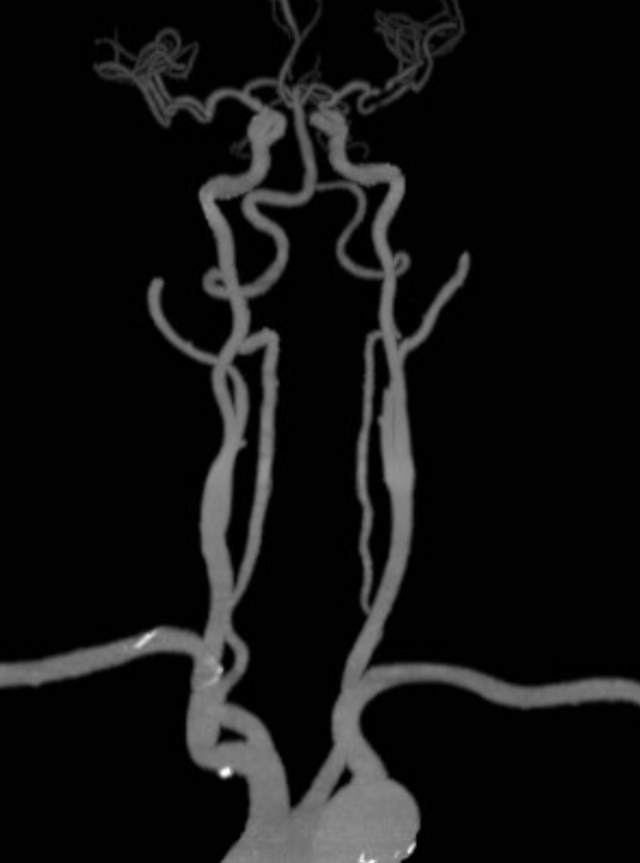

70岁老年男性,3个月前急性脑梗塞,尽管缺血性发作后及时在医院给予了“静脉溶栓”、药物和康复治疗,3个月后仍然存在言语含糊、头胀、记忆力减退和右侧上肢肌力减退,还伴有间断心悸等表现。初步的影像学检查发现左侧大脑中动脉M2段重度狭窄。家属一直彷徨在外科干预和药物保守治疗的选择中,干预吧,怕出现意外;

不干预吧,毕竟残存了一些功能障碍,还可能存在再次卒中的风险。通过多学科诊疗(MDT)和脑血管造影(金标准)后,进一步确认了狭窄的存在,左侧大脑中动脉上干血管存在重度狭窄,下干轻度狭窄。手术的难度在于狭窄的部位处于血管弯曲的部位,另外还要为下干预留日后可能干预的空间。